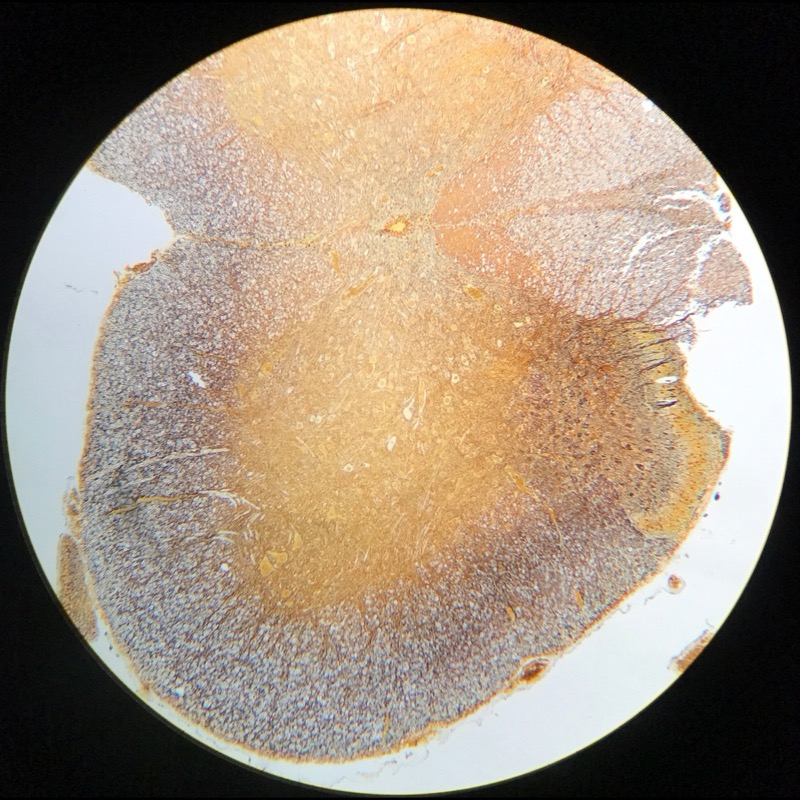

| 1:8:3 | Cerebellum cortex | ![]() ![]() ![]() ![]() |

| 1:8:4 | Cerebellum cortex, Gallocyanin | ![]() ![]() ![]() ![]() |